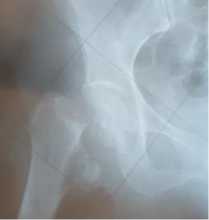

Gambar 2. Fraktur kolum femur kanan salah satu sampel

Pelaksanaan operasi AMP pada fraktur kolum femur di BRSUD Kabupaten Tabanan sesuai dengan standar pelayanan secara nasional. Teknik approach insisi dari anterolateral merupakan pendekatan umum bagi setiap pasien. Prosedur AMP yang identik dengan cemented dan un-cemented menjadi pertimbangan operator dan disesuaikan dengan indikasi durante op.